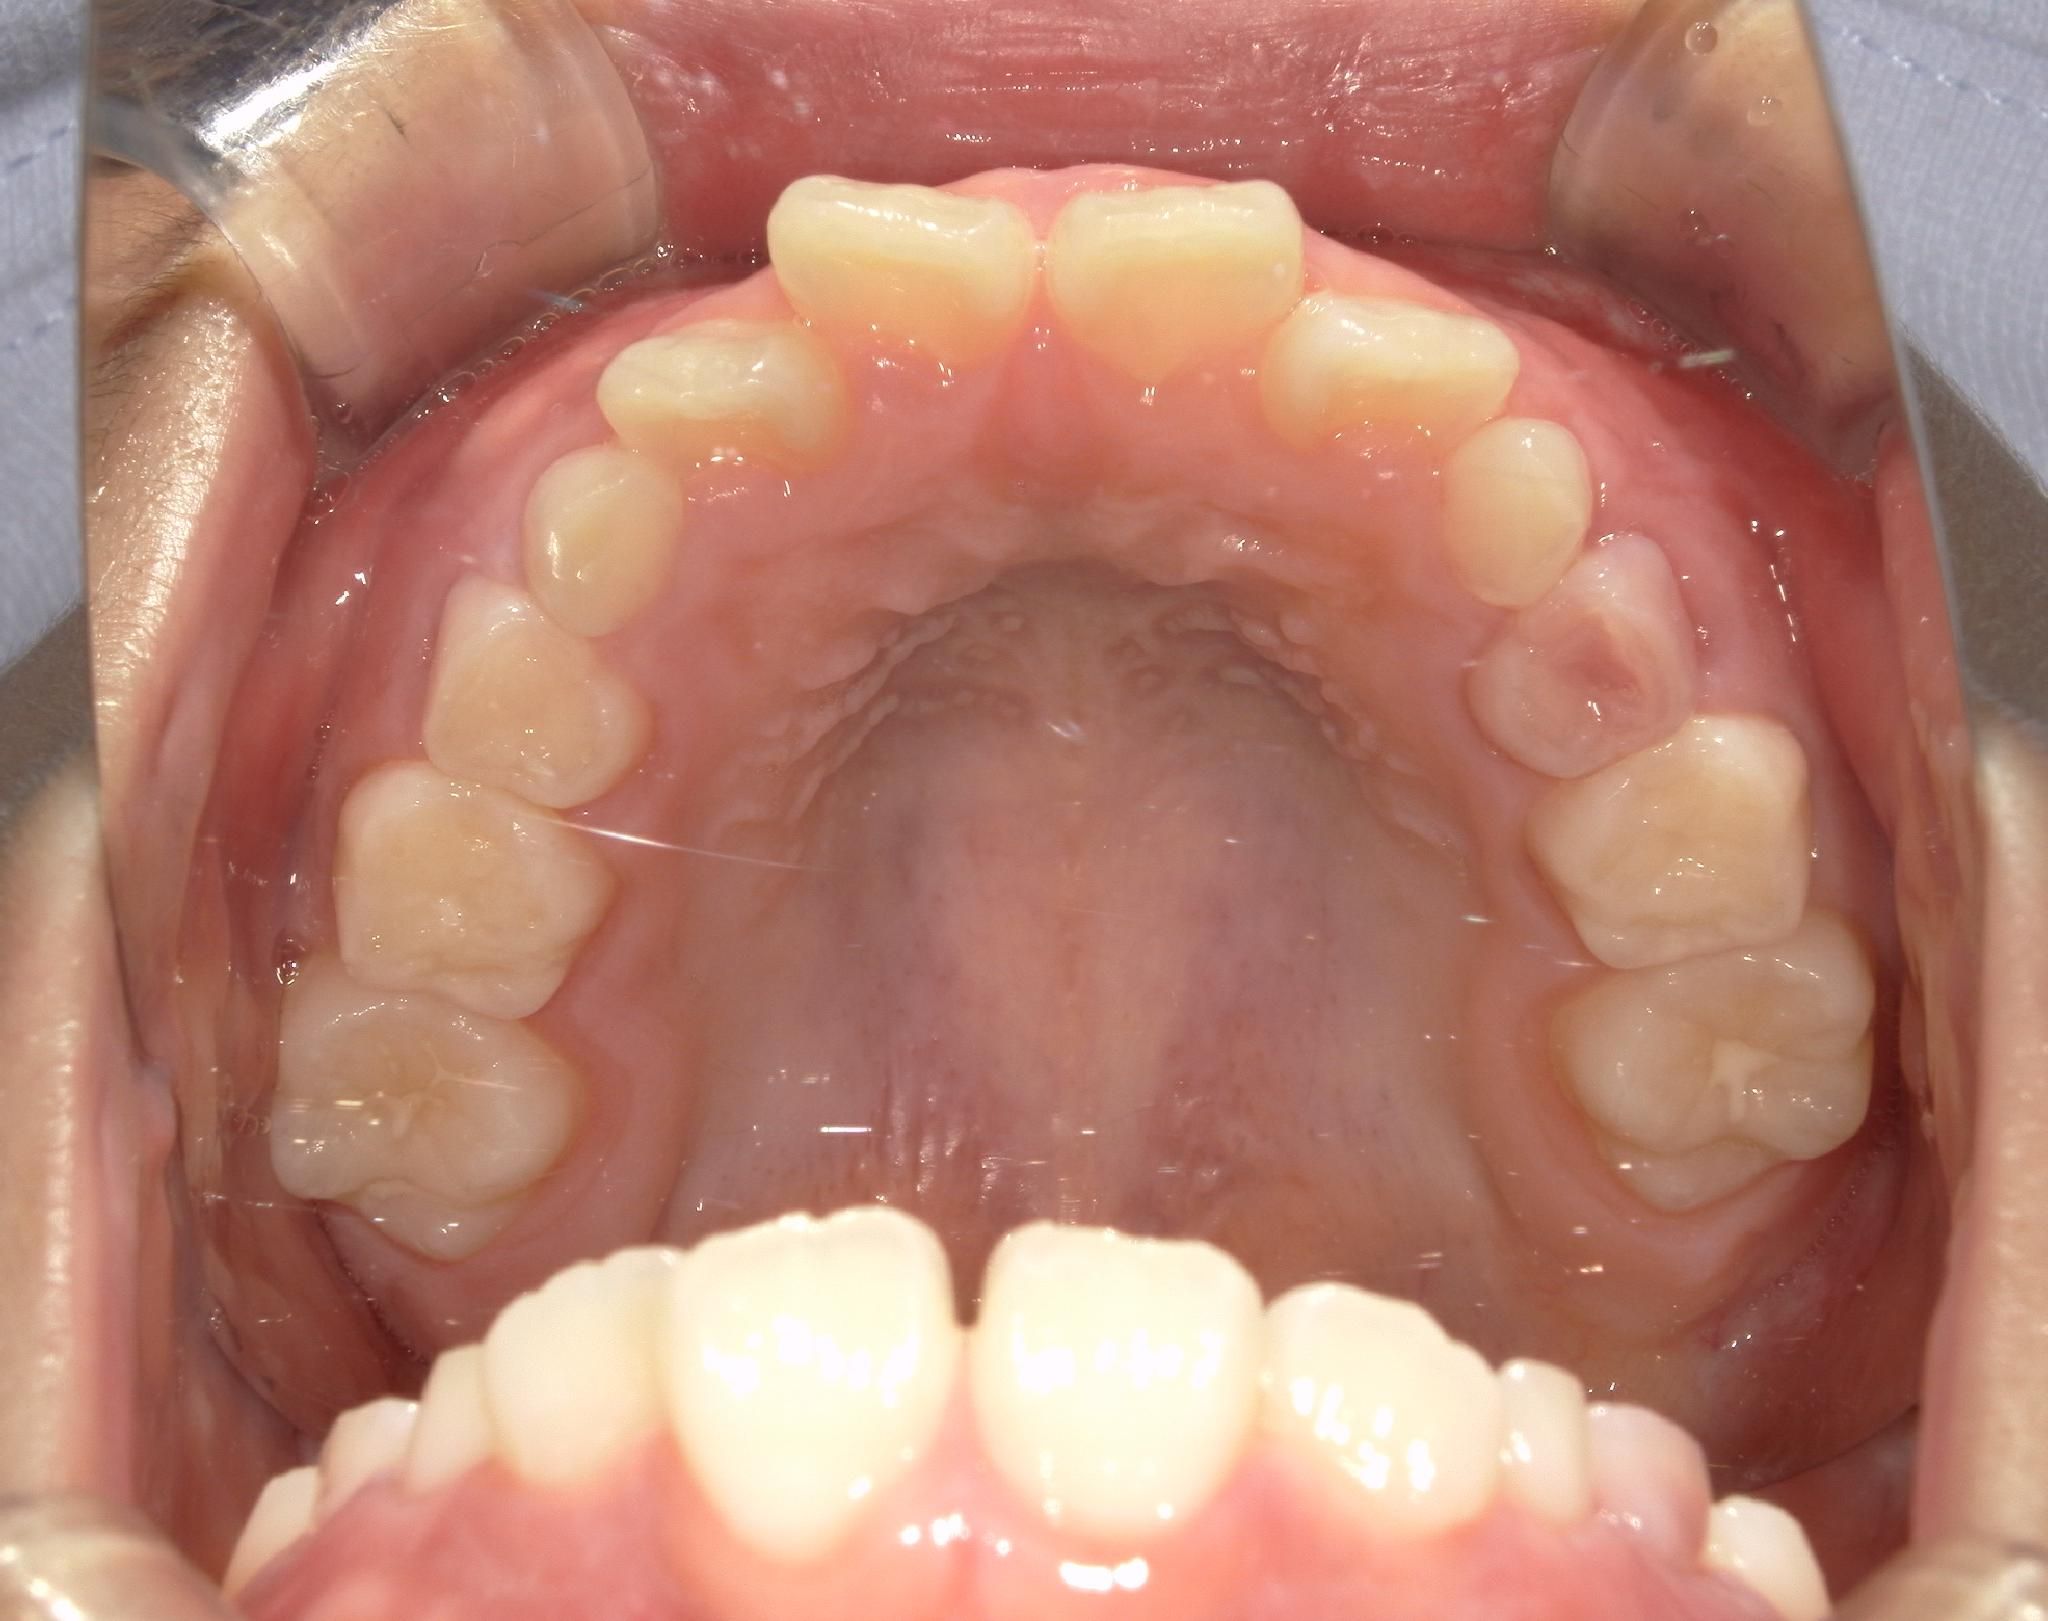

治療中 During treatment

上顎がバイオブロックにより広がり、すき間ができています